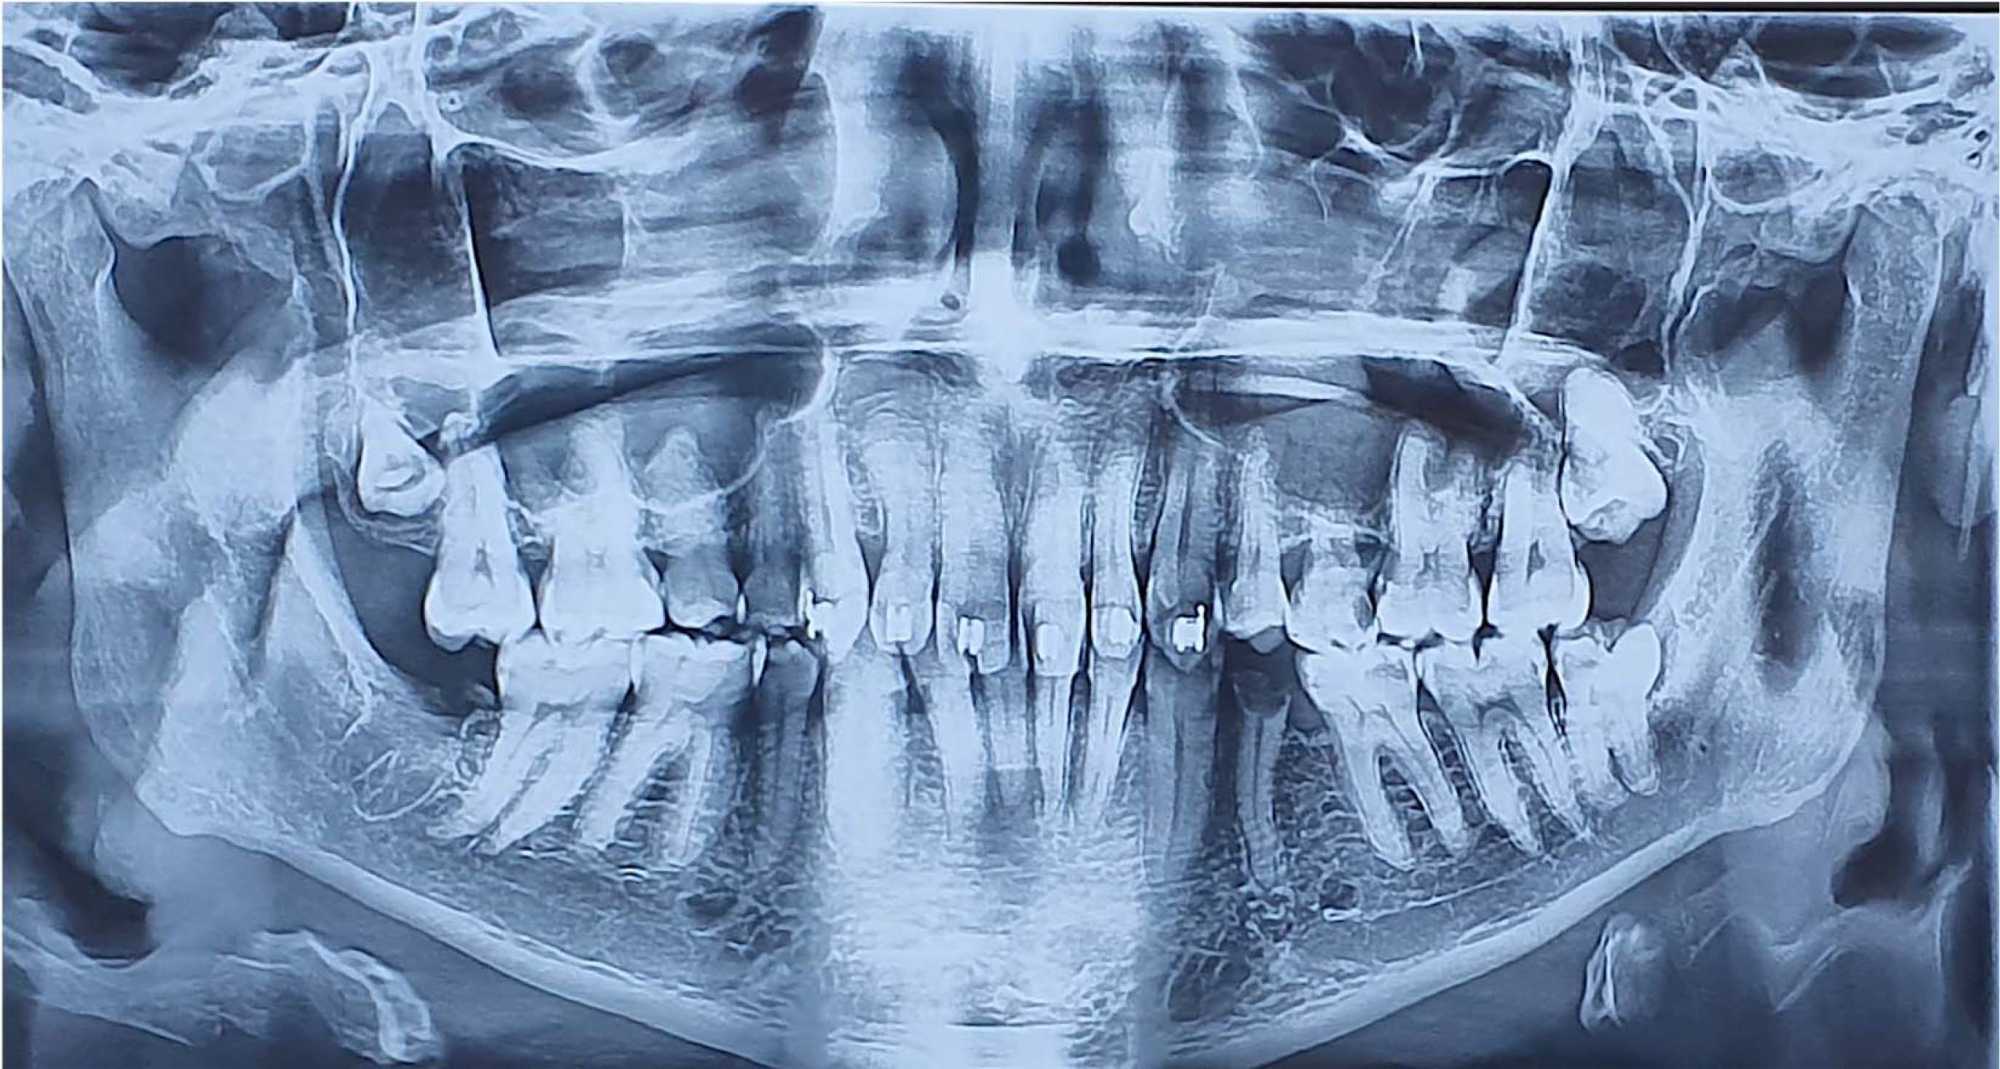

A 28-year-old male patient, a non-smoker in good general health, was referred to the Department of Surgical Odontology with complaints of persistent numbness in the right lower lip and chin following the surgical extraction of the right mandibular third molar. The patient reported no improvement in symptoms 10 days after the procedure. Clinically, he presented with complete numbness and loss of sensation affecting the right half of both the lower lip and the chin. A panoramic radiograph revealed close proximity between the extraction site and the inferior alveolar nerve (IAN) (Figure 1).

Figure 1. Panoramic radiograph: contact of the site of the right mandibular tooth with IAN.

A panoramic radiograph showed contact between the mental foramen and the site of tooth 35 (Figure 4).

Figure 4. Panoramic radiograph: contact of the site of extraction of tooth 35 with the mental foramen.

A panoramic radiograph confirmed the absence of tooth 48 and showed evidence of bone healing (Figure 6).

Figure 6. Panoramic radiograph: Absence of tooth 48 with signs of healing bone.

A panoramic radiograph showed involvement of the IAN within the cystic lesion (Figure 8).

Figure 8. Panoramic radiograph showing the disappearance of IAN canal and its submergence in the radiolucent lesion from tooth 48 to the roots of tooth 43.